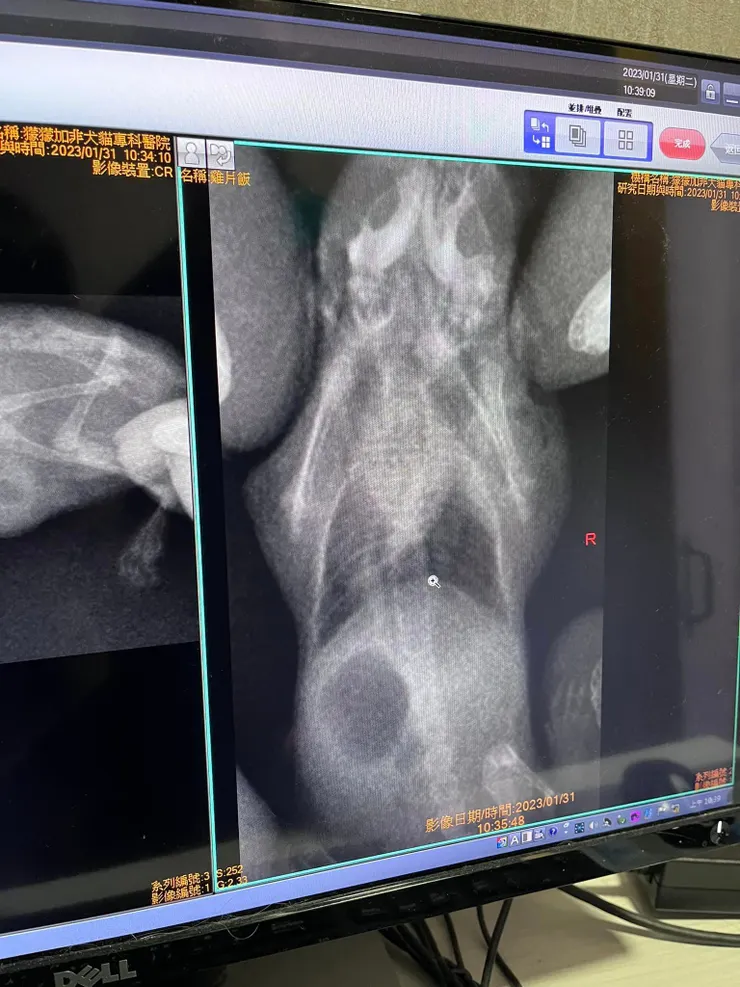

- 照兩張X光照,顯示鼻腔有感染症狀,及左邊肺部混濁。

初步判定為肺炎,呼吸道感染,推測是雞片飯喝水嗆到,需留意溫度及呼吸。另外心臟部分有提出雞片飯心臟功能較弱,日後需多加留意,但非造成現況主因。